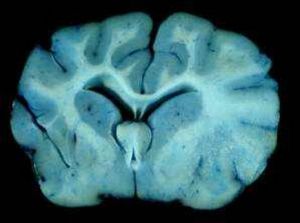

腦苷脂半乳糖苷酶葡萄苷脂醯鞘氨醇脂質貯積病1882年P.C.E.戈謝首先描述,又稱戈謝氏病。是最常見的遺傳性糖脂代謝病。為常染色體隱性遺傳。由於葡萄糖腦苷脂酶活性降低,從白細胞和紅細胞膜來的葡萄糖腦苷脂(即葡萄苷脂醯鞘氨醇)分解代謝受阻,不能分解為葡萄糖及醯基鞘氨醇,沉積於單核吞噬細胞系統(肝、脾、骨髓等臟器)。此病可見於任何年齡,有嬰兒型、幼兒型和成人型。嬰兒型於半歲內起病,病情急,兇惡,初期有肝脾腫大,繼而顱神經和腦幹嚴重受累,兩年內死亡。幼兒型於半歲以後發病,病情呈亞急性,內臟和神經系統皆可受累。成人型為慢性,可於出生後至成年時期內發病,一般不侵犯神經系統,主要表現為肝脾腫大,四肢骨關節痛,皮膚有棕黃色色素沉著。可因脾梗塞和脾破裂而引起急性腹痛。脾功能亢進可使血小板減少而有出血傾向。

對曾患戈謝氏病孕婦的胎兒或雙親是純合子或雜合子戈謝氏病的胎兒,培養從羊膜腔穿刺獲得的胎兒細胞,測定提取液中的葡萄糖腦苷脂酶,可鑑定胎兒是否有戈謝氏病。酸性脂酶缺乏常染色體隱性遺傳。酸性脂酶主要功能是水解低密度脂蛋白中的膽固醇脂,使它們從血漿中被周圍組織清除。此酶缺乏時,膽固醇脂和甘油三酯在身體許多組織中沉積。臨床表現主要有兩種:①沃爾曼氏病。1956年由M.沃爾曼首先描寫。是一種脫髓鞘疾病。主要為嬰兒患病,出生後即表現虛弱、肝脾大、腹瀉、腹脹及其他胃腸道症狀,腎上腺鈣化,智力發育落後,患兒很少能生存到1歲。②膽固醇脂貯積病。較為良性,有時到成年才被診斷。體內脂質廣泛沉積,肝腫大,常有高β-脂蛋白血症、早期動脈粥樣硬化,很少有腎鈣化。